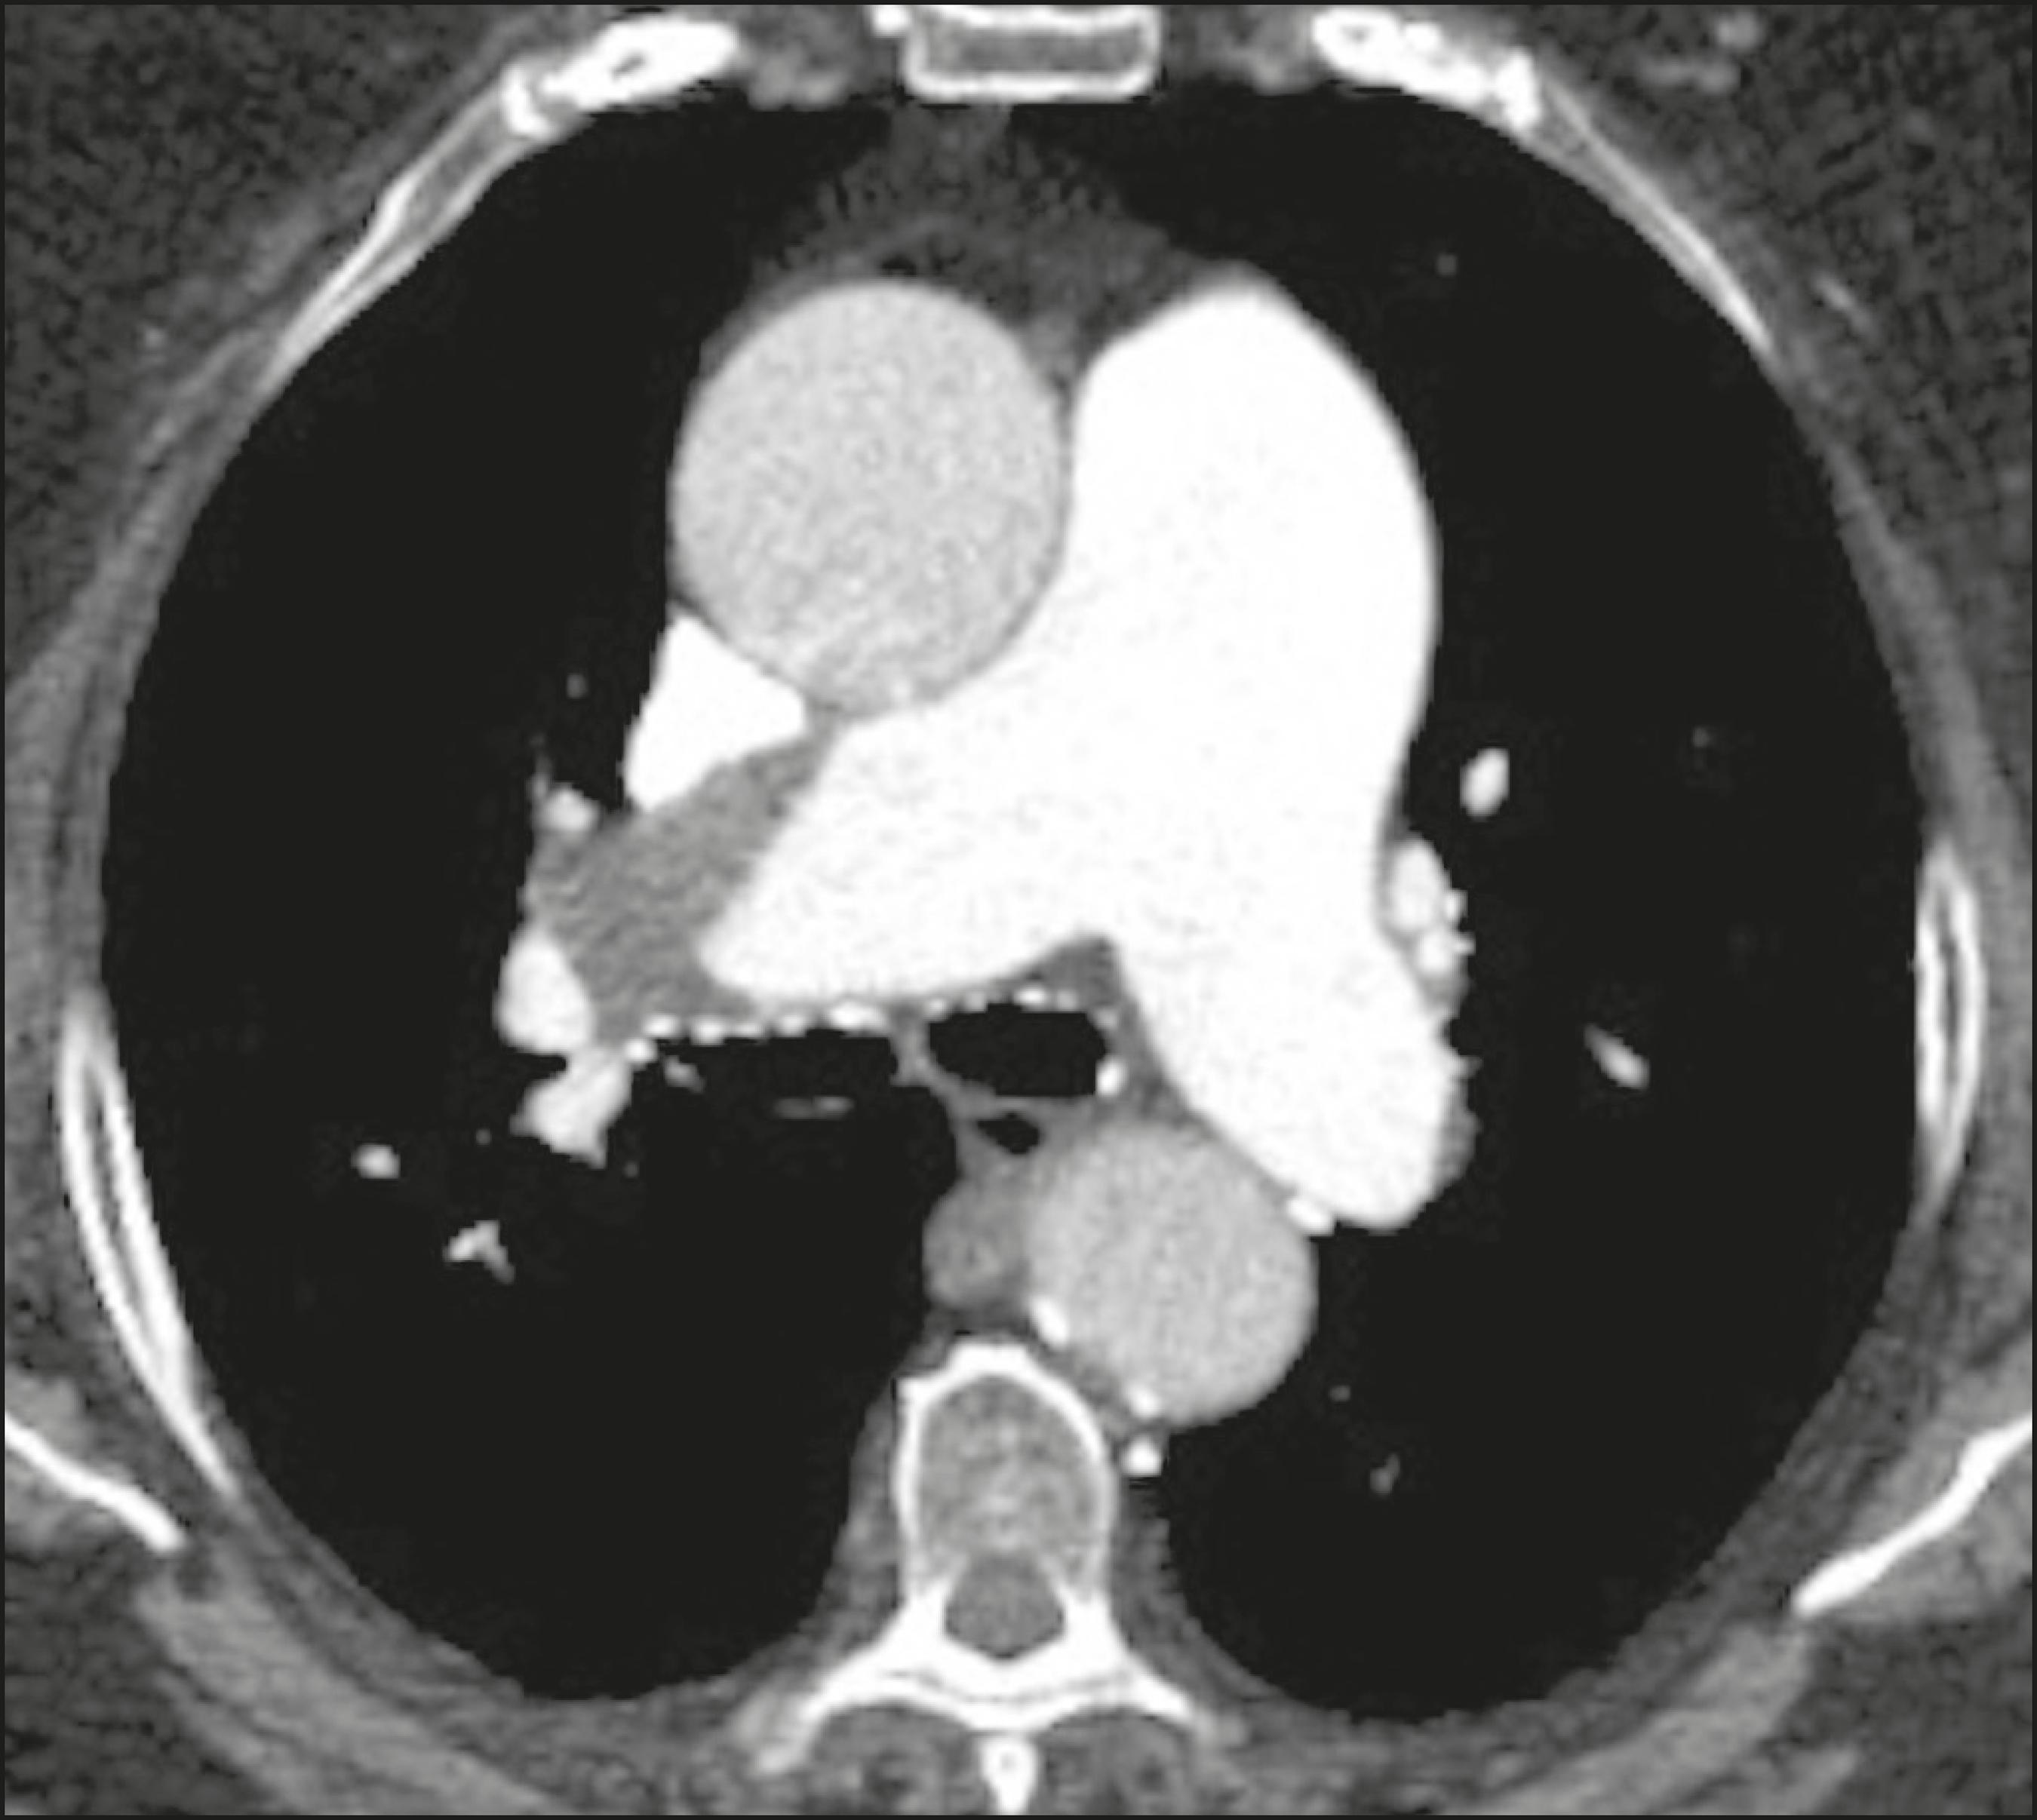

Protocolo técnico e cuidados no exame de tomografia para investigação do tromboembolismo pulmonar.

Saiba mais